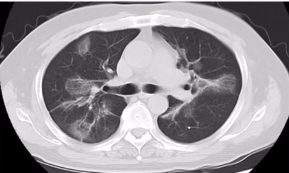

反晕征伴随条索影,指示机化性肺炎

图源:张嵩《诊断必备:肺部 CT 的诊断技巧及误区》

反晕征最常见于机化性肺炎。本病例双肺伴随多发磨玻璃影、反晕征、条索影。最后诊断为机化性肺炎,使用激素治疗后效果良好。